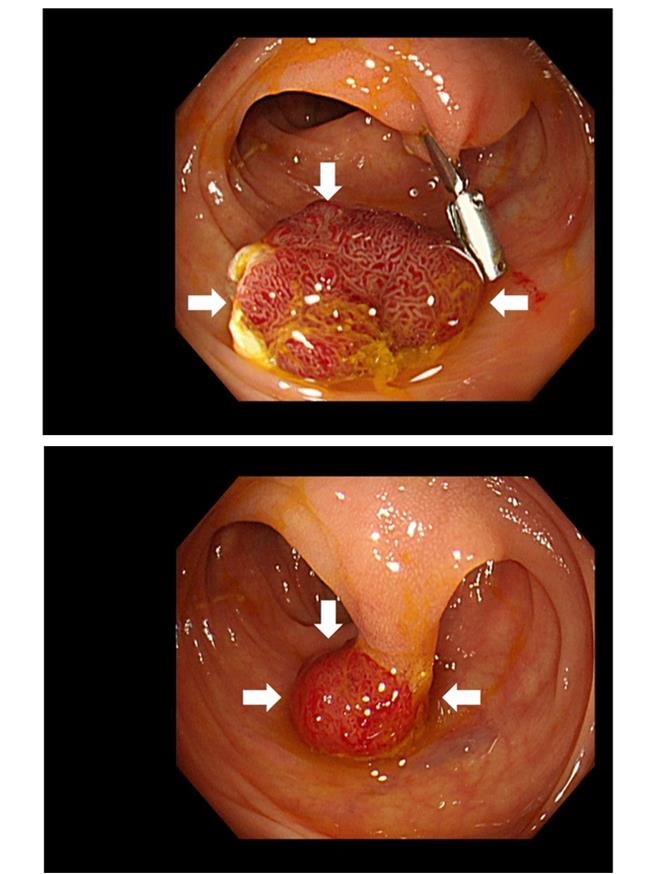

若粪便潜血检查呈阳性,民眾应尽速就医,由医师评估安排大肠镜检查。林彦廷说,大肠镜除可直接观察肠道内状态,亦能即时对溃疡或瘜肉等可疑的癌前病变进行切片或切除,检查结果粗分正常、发现瘜肉或其他病灶以及发现大肠癌。接受大肠镜检查前,受检者需进行1至2天饮食控制并服用专用泻剂,检查过程中可能造成些许不适感,若想轻松度过也可与医师讨论麻醉进行。